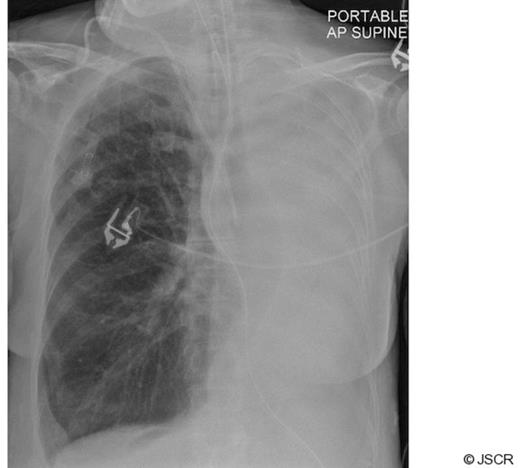

Arterial oxygenation improved quickly afterwards, allowing the inspired fraction of oxygen to be reduced to 0.3, and there were no complications from the procedure. A subsequent radiograph confirmed re-inflation of the left lung field (Fig 4).